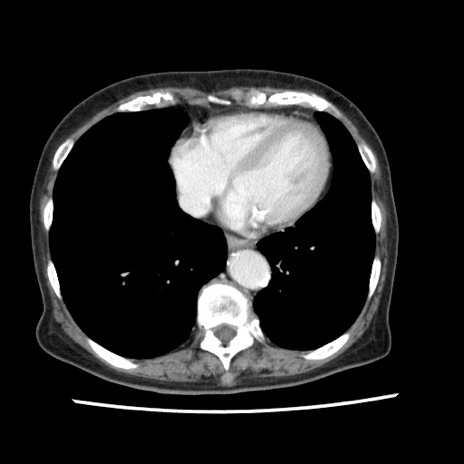

矢状断像

【症例】80歳代女性

【主訴】腹痛

【現病歴】8時間前から腹痛あり来院。

【既往歴】糖尿病、脂質異常症、子宮体癌にて子宮全摘術

【身体所見】意識清明・会話良好だが腹痛で苦悶様、全腹部にわたって反跳痛と圧痛あり

【データ】WBC 13600、CRP 0.14、LDH 224、CK 90